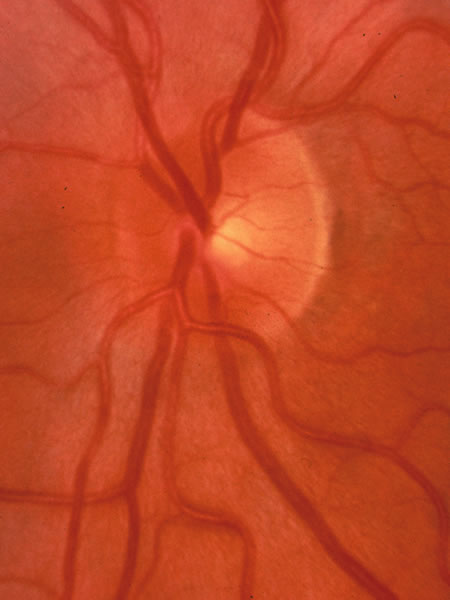

Usually all other forms of optic nerve disease (and inner retinal disease) produce simple atropy of the disc without cupping (Figs. 34 to 36), but occasional cases of cupping have been seen with anterior ischemic optic neuropathy, particularly due to giant cell arteritis (Figs. 37 and 38).

Fig. 34. Photograph of a normal left eye at a time when the right eye had an attack of anterior ischemic optic neuropathy.

Fig. 35. Same eye as Figure 34 during a subsequent attack of ischemic optic neuropathy.

Fig. 36. Same eye as in Figure 34 one year later, with atrophy but no excavation.